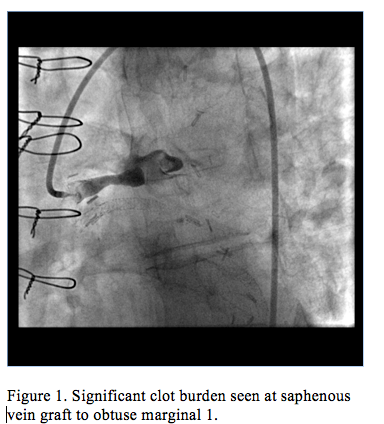

Cardiac catheterization revealed an occluded SVG to OM1 with TIMI flow 0 and possible thrombus (Figure 1, Video 1), a patent LIMA to LAD, an occluded stent within the SVG to Diagonal 1, and a patent SVG to RCA. A 0.014˝ x 135 cm Trailblazer catheter coronary guidewire engaged the SVG to OM1 graft and crossed the lesion. A temporary pacemaker and an intra-aortic balloon pump were placed due to bradycardia and hypotension. A 5 Fr Export catheter was then passed to the thrombus and approximately 15 mL of thrombus were aspirated. Repeat aspiration resulted in a collection of 20 mL of thrombus; however, a significant amount remained (Figure 2, Video 2). A 0.041" x 135 cm TrailBlazer catheter was then advanced to the thrombus and 8 mg of intracoronary abciximab were injected.